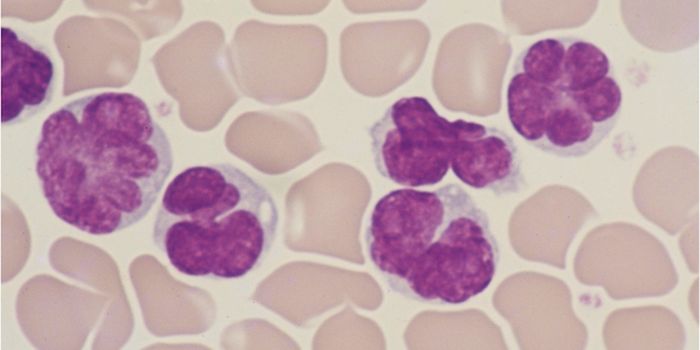

DEC 23, 2015ImmunologyInhibiting large cellular populations of myeloid derived suppressor cells (MDSCs – look up) could be a new therapy ...